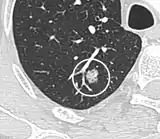

A lung nodule or pulmonary nodule is a relatively small focal density in the lung. A solitary pulmonary nodule (SPN) or coin lesion,[1] is a mass in the lung smaller than three centimeters in diameter. A pulmonary micronodule has a diameter of less than three millimetres.[2] There may also be multiple nodules.

CT scan